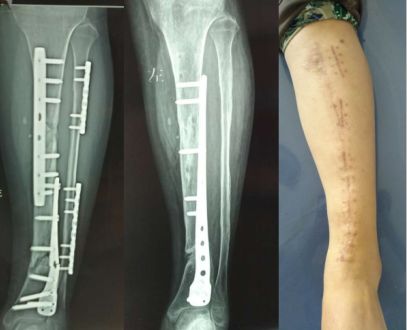

胫骨远端简单骨折选用钢板固定没有实现坚强固定,钢板承受应力,孔处应力集中断裂

更换长钢板后愈合

下一例:是胫骨骨折局部钢丝螺钉内固定太多干扰骨愈合,骨不连接钢板迟早断裂。

开放骨折,软组织损伤严重,骨不连接导致钢板断裂。应当在伤口愈合后及时干预植骨